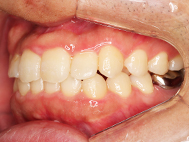

Before

| 症状 | 上顎前歯部叢生 |

上の前歯がハの字隣の歯が引っ込んでいる

前歯のガタガタが気になるとの事で来院されました。

装着が目立ちたくないとの事でアライナ-での矯正を希望されました、歯の間を削り少し歯の幅をスリムにして綺麗なアーチに並びました。